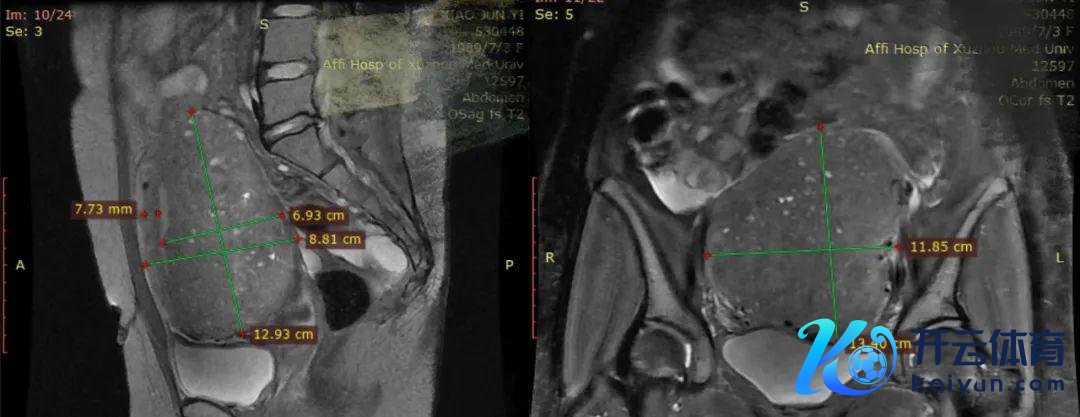

一年后再次找我的时辰,还是舍弃生二胎的念念法了,痛经严重到每次月事期需要休息2天。那时的子宫还是比拟大,109*111*87mm,子宫后壁可见局部低回声67*68mm,上方的图是核磁共振的情况,不错看到她子宫前壁是畴昔的,7.7mm,后壁肌层很厚,69mm,很妥当腺肌症的特质,90%的腺肌症病灶王人是在后壁的,后壁的肌层内部有好多的白色点点,代表着是子宫腺肌症的出血性病灶。